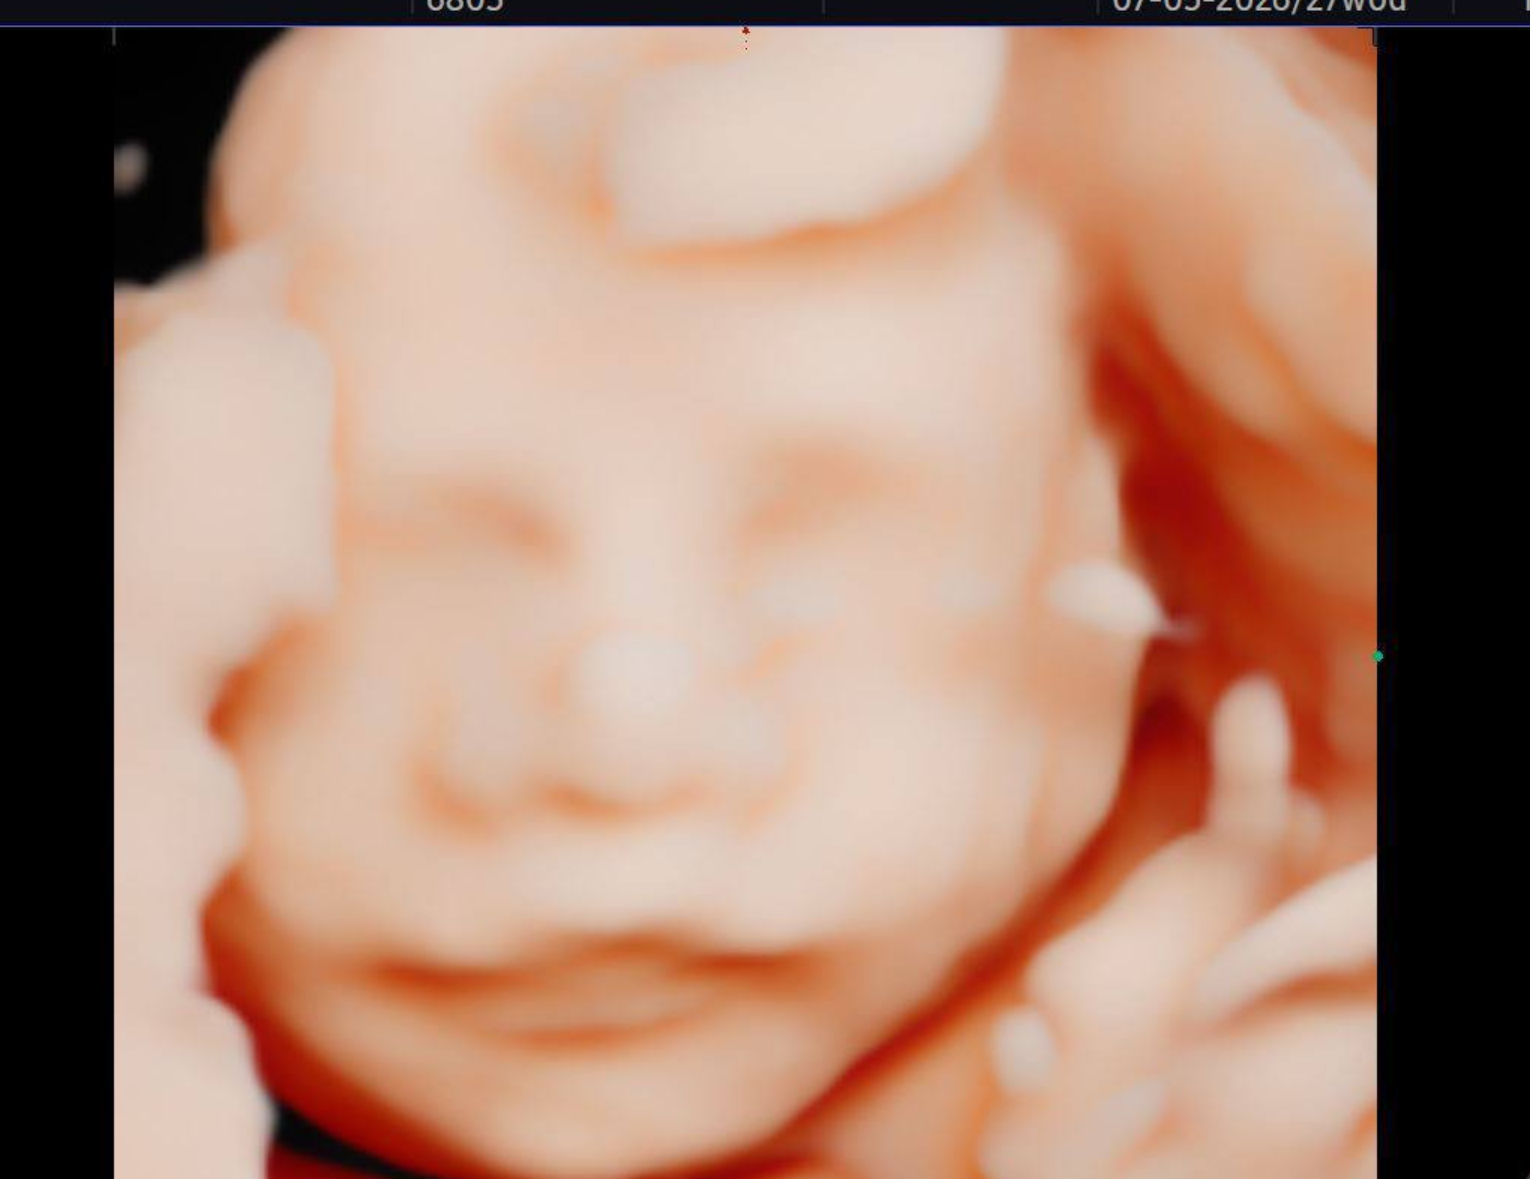

25週,一切平安,又一寶寶四維檢查順利通過,一切指標健康。

這不僅僅是一次順利的產檢,更是小天使在向世界發出的第一次‘健康宣言’。願這份喜悅持續,期待不久後的如約相見。